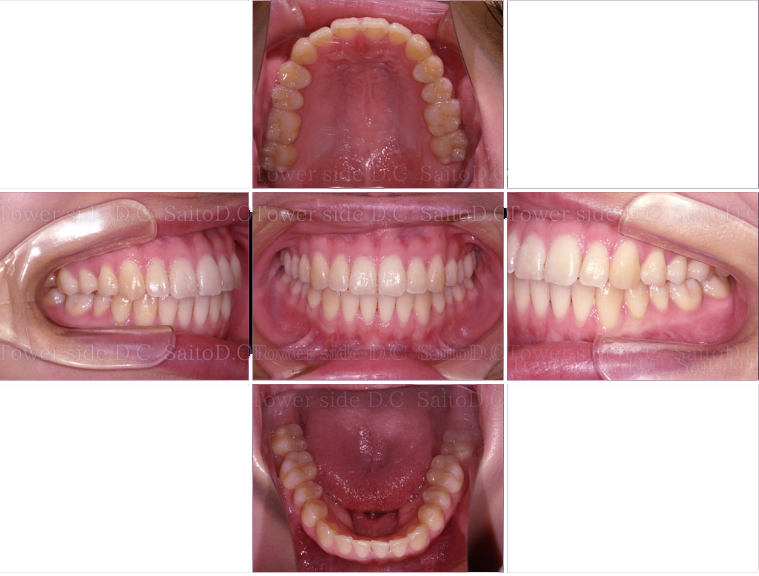

症例11CASE 11

|20代歳(女性)|

インビザライン症例

症例(施術前)

症例(施術後)

主訴 歯のガタガタを綺麗にしたい

状況

• 切端咬合

• 左上犬歯部反対咬合

治療費 326,700円(税込)(自由診療)

治療期間 7ヶ月

治療内容 マウスピース矯正を使用し、前歯と奥歯のディスキングを行いスペースをつくり、正しいかみ合わせに改善した。噛み合わせ、歯並びは改善されその後保定装置(リテーナー)を使用し安定している。